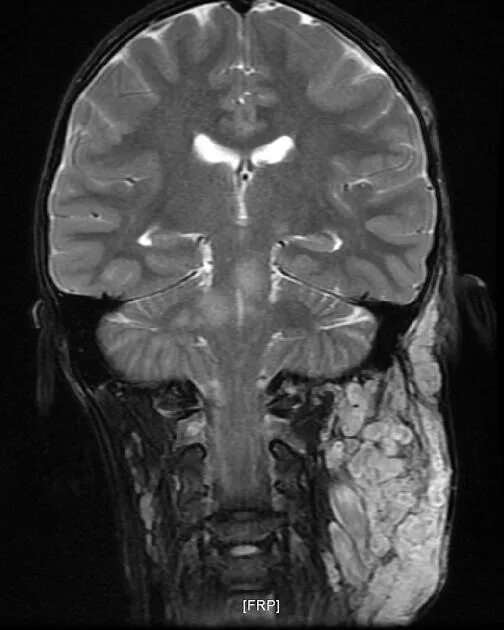

Нейрофиброматоз мрт